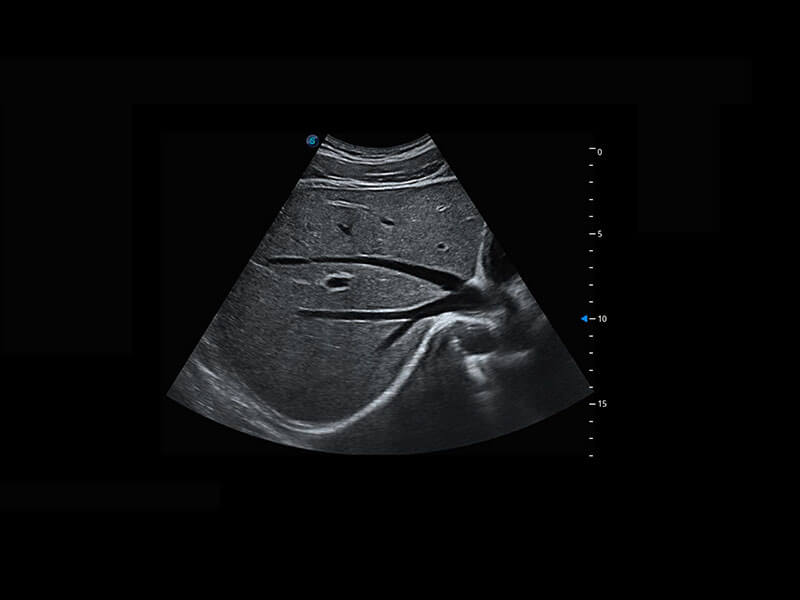

四腔切面

四腔心血流

右室双出口

胎心容积成像